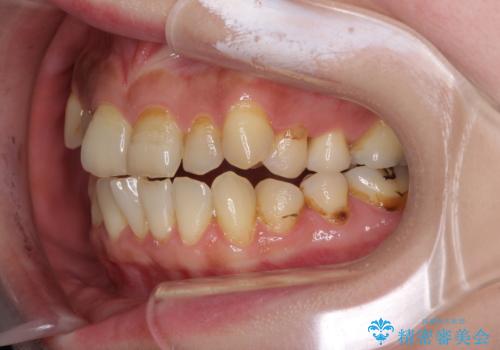

- 歯列不正と、どこで咬んで良いのか分からない咬み合わせを気にして来院された患者様です。

下顎骨は左側にシフトしており、咬み合ったときには奥歯と前歯の一部しか接触していない状態でした。

骨格的な左右差は歯列矯正は改善できないため、上下歯列が全体的に接触することをゴールとしてインビザラインにて矯正治療を行うこととしました。